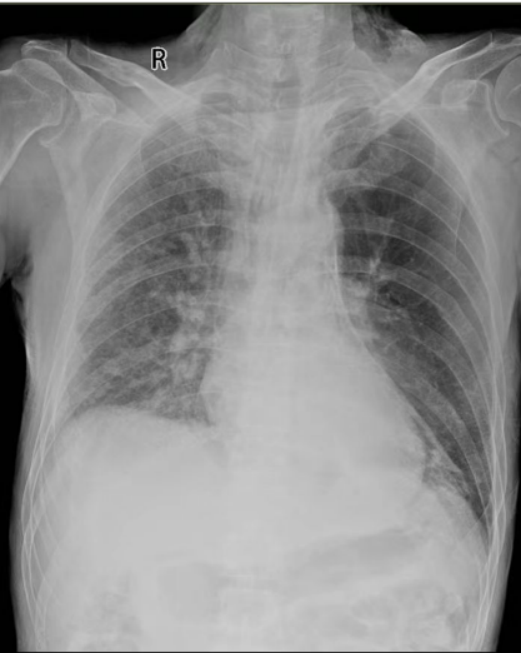

2024年12月30日,患者突发喘憋加重,氧合无法维持(SpO2 84%),伴体温明显升高(体温38.8℃)。血气分析示PaCO2 26.50 mmHg(↓),PaO2 51.90 mmHg(↓);床旁胸片示左肺透亮度增高,气管向右侧移位(图2)

图片

2  患者床旁胸片(2024-12-30)

考虑左主支气管阻塞加重,产生活瓣效应致左上肺过度充气,不除外感染加重、免疫检查点抑制剂相关肺炎进展,调整抗感染方案为美罗培南+万古霉素,甲泼尼龙加量至40 mg qd,并紧急行支气管镜介入治疗。